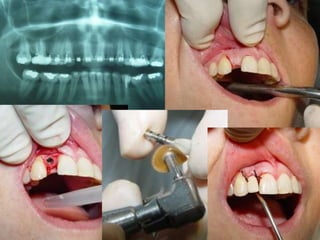

PLANEJAMENTO CIRÚRGICOEXAMES POR IMAGENS:Radiografia Panorâmica para implantes

PRIMEIRA FASE CIRÚRGICAMOTOR PARA CIRURGIAPRIMEIRA FASE CIRÚRGICAKITS CIRÚRGICOSTipos de implante e indicações

Seqüência de Brocas

Avaliação Clínica no Momento da Instalação do ImplanteAparelhos especiais Osstell (mede por freqüência e ressonância)Avaliação Clínica (estabilidade)Torquímetro (mínimo 45 Newtons)Avaliação   radiográfica   ( durante   a instalação,  mede  a  distância   entre implantes e estruturas adjacentes)